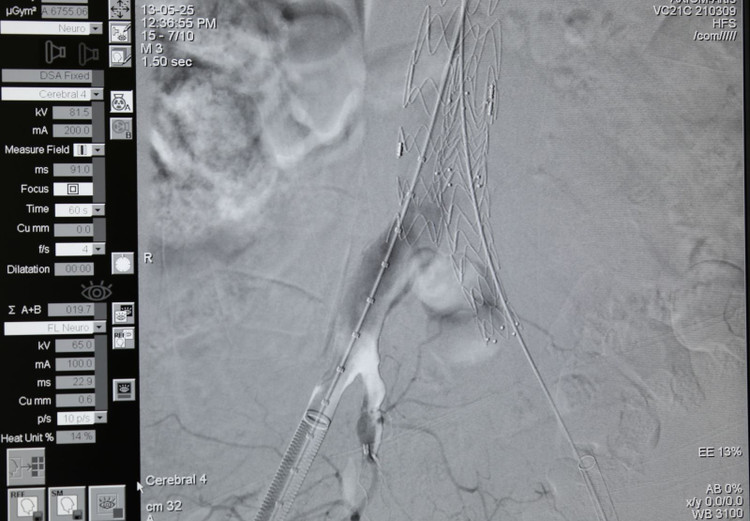

can-theip-2.jpg

Hình ảnh Stent graft được đặt tại khối phình động mạch chủ - Ảnh BVCC

Ca can thiệp do BSCKII Trần Quang Định, Trưởng khoa Phẫu thuật và Can thiệp Tim mạch và Bs.CKII Nguyễn Khắc Linh, Trưởng khoa Nội B thực hiện với sự hỗ trợ của chuyên gia.

Ê-kíp tiến hành đặt stent graft tại vị trí khối phình động mạch chủ bụng đoạn dưới thận và 2 stent nhánh vào động mạch chậu hai bên.

Stent graft được đưa vào đoạn mạch bị phình rộng tạo thành một giá đỡ vững chắc, có tác dụng như một màng bọc bảo vệ thành động mạch chủ bị tổn thương, ngăn nguy cơ vỡ khối phình.